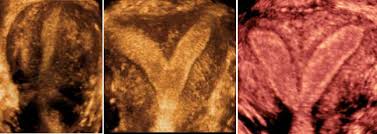

سونوگرافی واژینال در هفته ششم بارداری

در هفته ششم بارداری کیسه حاوی نطفه مشاهده و گاهی اوقات نیز ضربان قلب شنیده می شود. امکان دارد دو قلو یا چندقلو بودن جنین نیز مشخص شود. اما یک جنین به راحتی قابل مشاهده نیست. گاهی اوقات ضربان قلب در یک کیسه شنیده می شود و تکرار سونوگرافی ضربان قلب دوم را نیز نشان می دهد. ممکن است طی سونوگرافی رشد یک کیسه مشاهده شود در حالی که دیگری هنوز خالی است. این پدیده سندروم قل ناپدید شده نامیده می شود.